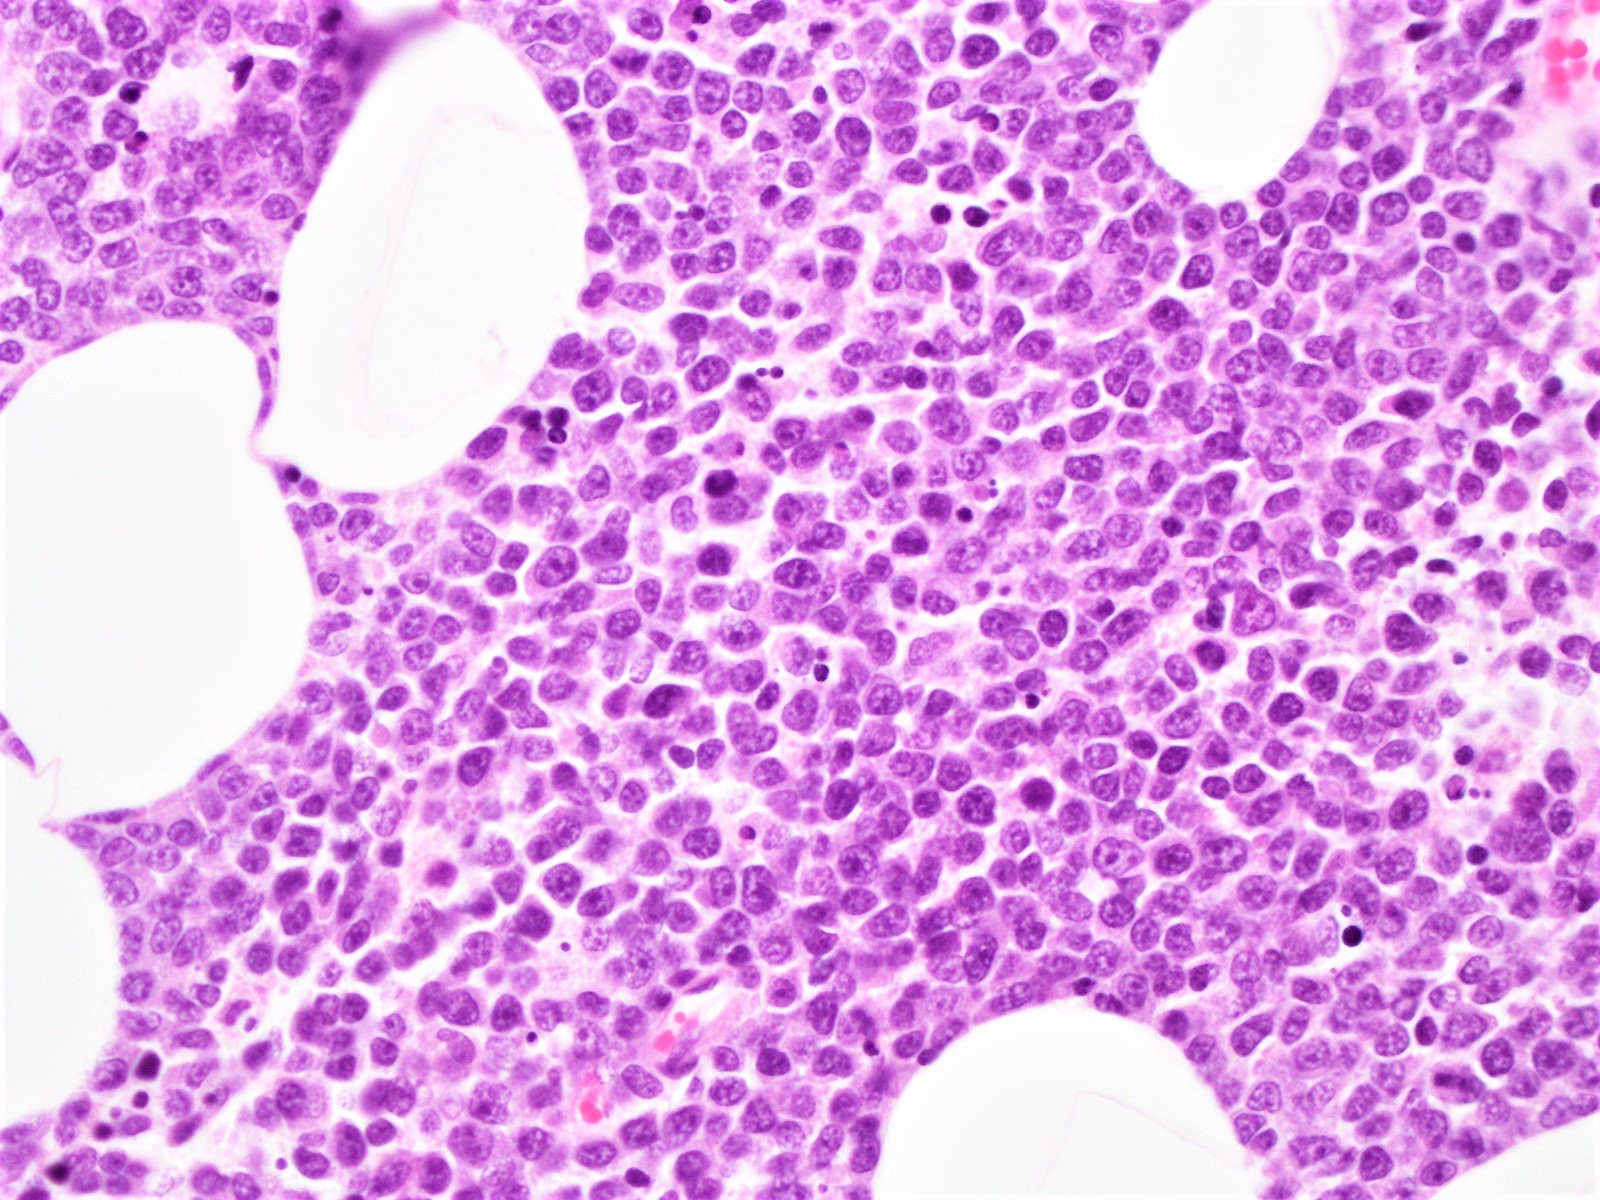

Microscopic (histologic) description

- Blastoid variant

- The growth pattern is usually diffuse

- Less frequently nodular pattern

- Starry sky appearance common in low power

- Intermediate sized cells

- Monotonous population

- Immature chromatin

- Scant cytoplasm

- High mitotic rate > 20 - 30/10 high power fields

- Resembles, in part, lymphoblastic lymphoma

Microscopic (histologic) images